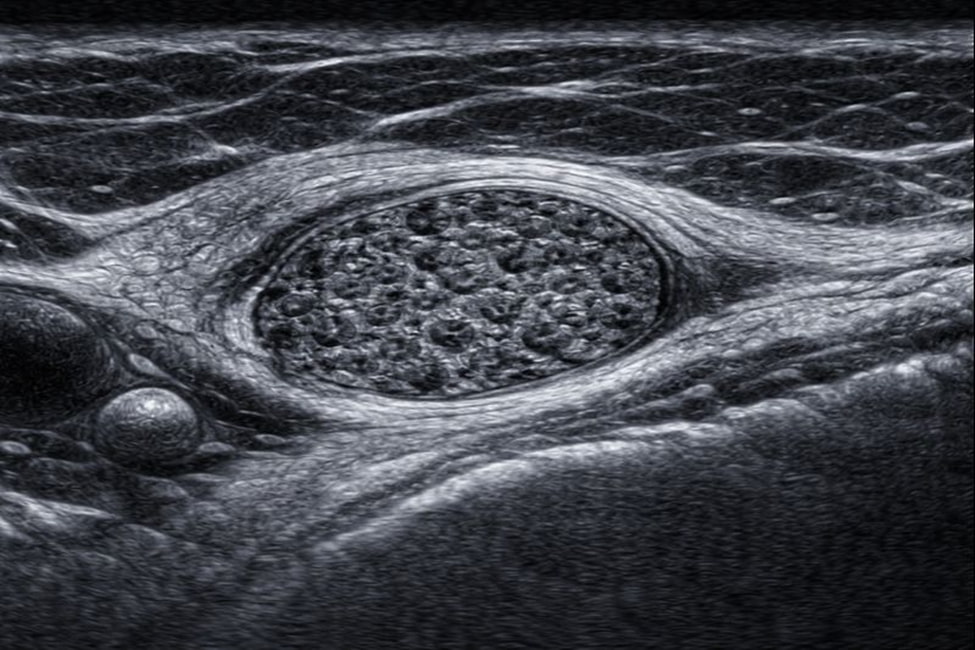

УЗИ периферических нервов — это неинвазивный метод, ультразвуковая визуализация, направленная на изучение нервных образований, которые расположены за пределами центральной нервной системы. Во время исследования врач детально рассматривает нервный ствол, его ход, толщину и взаиморасположение с окружающими структурами.

УЗИ периферических нервов дает возможность оценивать форму и структуру нервных образований, а также их эхогенные характеристики. Врач анализирует соответствие анатомическим ориентирам и выявляет отклонения от нормы.

Метод позволяет обнаруживать воспалительные изменения, утолщения, смещения и иные патологии, влияющие на характеристики нервной проводимости. Исследование отражает анатомический ход нерва и его взаимодействие с окружающими тканями, что имеет ключевое значение для постановки диагноза.